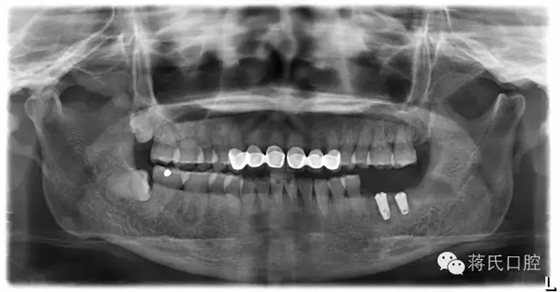

2.種植后全景片